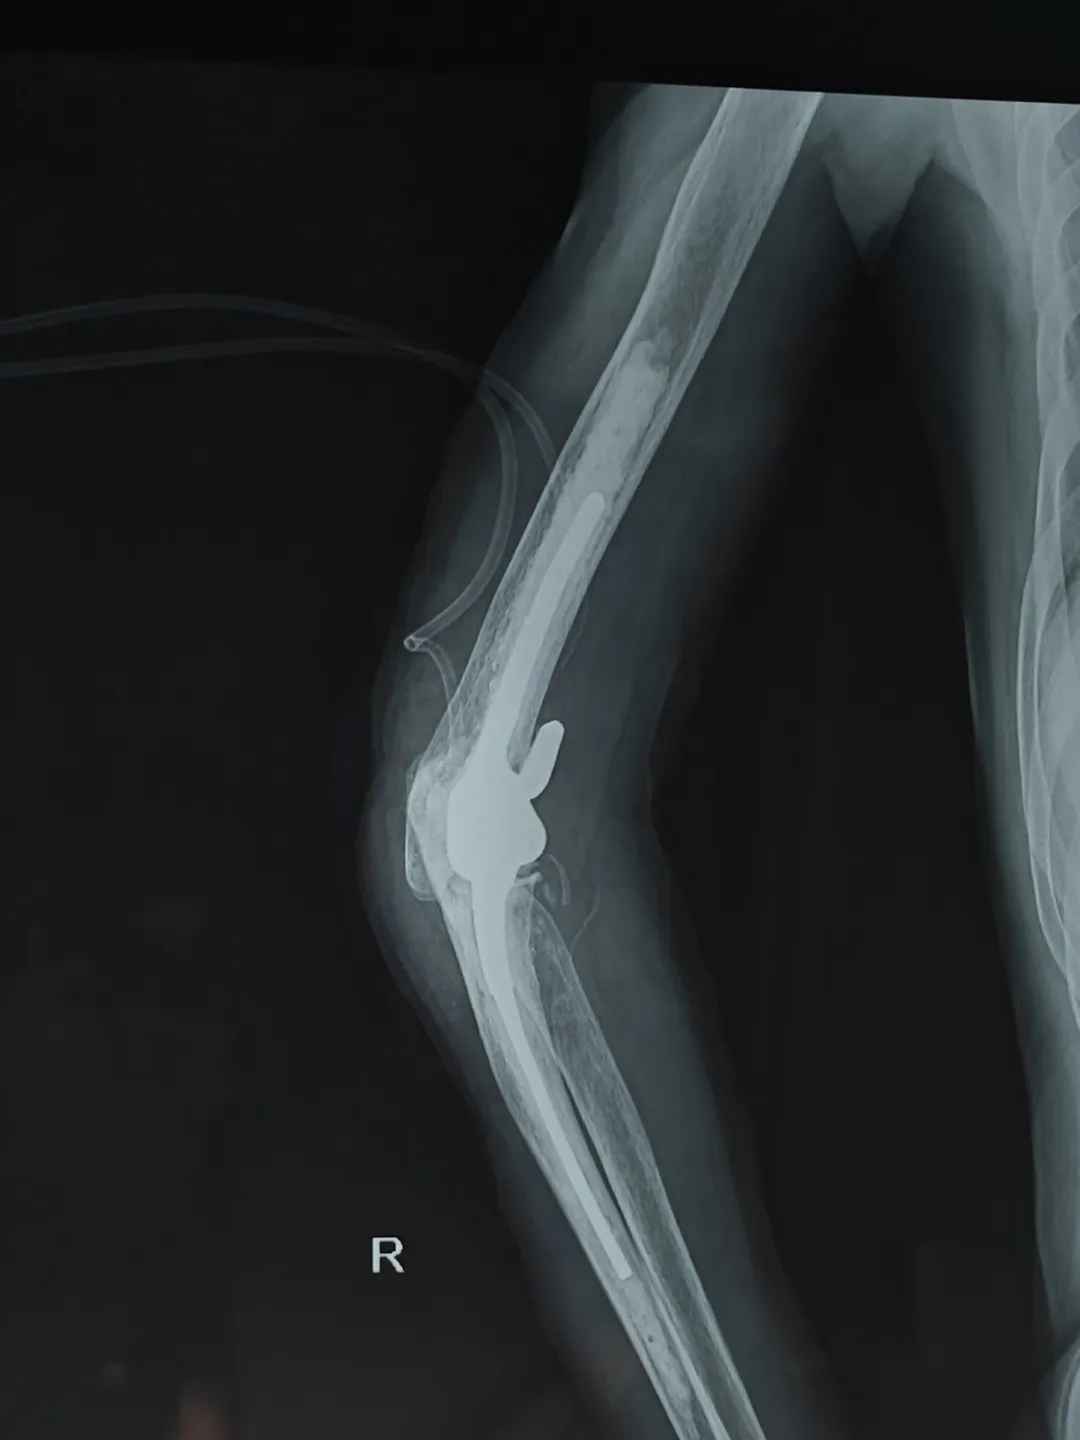

在李庭教授的指导下,91直播 创伤外科中心A区医护团队成功为患者实施手术。术后,患者一直积极配合医生的治疗方案,并严格遵守康复计划。通过一系列的康复训练和物理治疗,患者的身体状况逐渐好转,各项生理指标也逐渐恢复正常。

患者术后X光片

北京积水潭医院知名创伤骨科专家李庭教授,作为91直播 外聘教授,高度重视91直播 创伤急救外科学科建设,亲临91直播 进行全肘人工关节置换术的教学手术。整个手术过程行云流水,从细致的术前准备,到精确的手术操作,再到细致的术后管理,体现出李庭教授极高的专业水准和精益求精的手术理念。李庭教授每做一步都会对91直播 医生详细讲解,将多年的临床经验毫无保留地分享,这种传帮带的学术精神令人敬佩。李庭教授精湛的技术和丰富的经验,为91直播 创伤急救外科医生团队带来了难得的学习机会,规范了诊治流程,增加了四级手术率,同时也让患者和家属倍感安心。